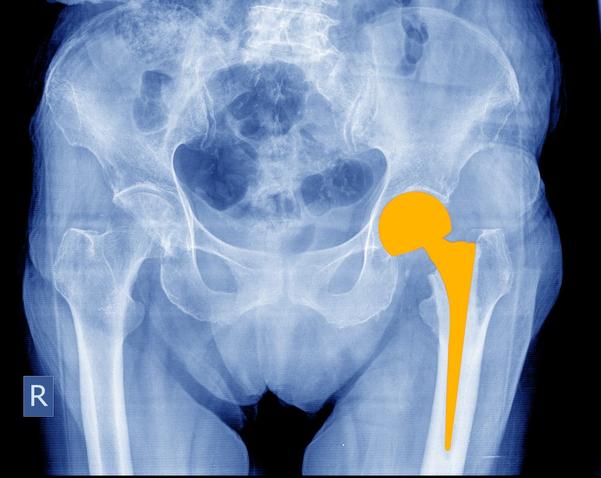

Orthopedic Surgeon, Joint Replacement Surgeon - Arthroscopy & Sports Injury, Trauma surgery

Fellow in Joint Replacement, Fellowship in Arthroplasty & Joint Replacement , Fellow in Arthroscopy & Sports Medicine , Fellowship in Pelvi-Acetabular Trauma & Adult Reconstruction , Fellowship in Robotic Arthroplasty